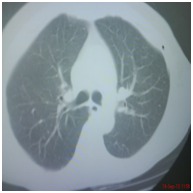

Sixty five year old gentleman is brought to emergency department with acute breathlessness. He had been symptomatic for last three months. He complained of persistent non productive cough followed by some hoarseness and lately breathlessness which was progressive in nature. He had been a current smoker with 25 pack years of smoking. He was hypoxemic on room air and was unable to lie flat. He denied symptoms consistent with COPD prior to his present illness lasting for three months. Routine blood chemistry was unremarkable. Echocardiogram showed normal left and right heart functions. Arterial blood gas revealed pH; 7. 35, PaCO2 of 45mmHg and PaO2 of 60mmHg of on 5LPM oxygen through simple mask. Chest diagram Figure 1 showed normal lung fields with normal hila, tracheal and cardiac contours. Injectable antibiotics, steroid, nebulised bronchodilators were started along with oxygen and non invasive ventilation. After two days of treatment he showed signs of improvement and was comfortable most of the times and tolerated removal of BiPAP for few hours. However, he preferred to maintain sitting posture even when in sleep and resisted lying down on the bed. He was noted to have paroxysmal respiratory distress requiring top-up nebulisation and reinstitution of NIV support and these events continued for next few days. Further imaging was planned in view of this unusual behaviour. Contrast enhanced CT scan of thorax was performed. Right paratracheal tumor was noted with extrinsic compression on trachea (Figure 2A-2C). Malignant growth obstructing trachea as the cause of his symptoms was discussed with the family. Bronchoscopy and stenting with involved risks were explained and informed and written consent was obtained. Videobronchoscopy was performed. Left vocal cord was immobile (Figure 3A). Subglottic trachea was circumferentially encroached by fleshy growth reducing the diameter to almost pin-hole size (Figure 3B & 3C). As bronchoscope was passed beyond the narrowed part the upper and mid tracheal lumen was wide open however encroached on both sides by infiltrating tumor (Figure 3D). Lower third trachea, primary carina and bronchi on both sides were wide and clear (Figure 3E). The dimensions were estimated and 6. 0cm hybrid Nitinol stent was placed in the trachea covering the tumor extension on both ends (Figure 4). Bronchoscope was withdrawn and patient breathed comfortably even in lying down position. Oxygen and BiPAP support were not needed anymore. Nebulization frequency was reduced and also the dose of steroid. Biospy from growth was consistent with moderately differentiated squamous cell carcinoma. He was discharged with advice to follow up with oncology for chemotherapy.

Figure 2a CT Scan: Right Paratracheal Mass.

Figure 2b CT Scan at level of carina.

Figure 2c CT Scan at level of carina.